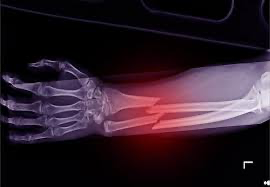

The fourth step is to seek medical attention as soon as possible. A broken bone needs to be properly diagnosed and treated by a medical professional. They will take an x-ray or other imaging to determine the extent of the injury and develop a treatment plan. This may include casting or surgery to realign the bone and promote healing.